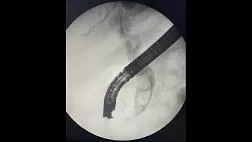

Единая эндоскопическая классификация поражений пищевода, желудка и толстой кишки с увеличением: пилотное исследование осуществимости

Оригинальное название Unified magnifying endoscopic classification for esophageal, gastric and colonic lesions: a feasibility pilot study